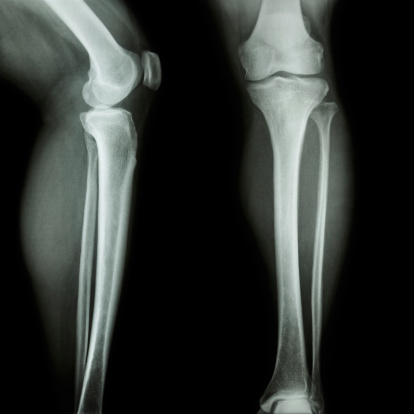

Анатомия человека: берцовая кость в деталях